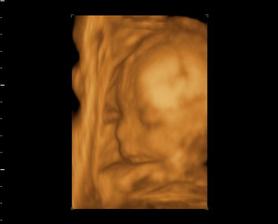

My a náš prvý očakávaný anjelik

Po roku dlhého skúšania sa nám konečne podarilo...Sme s manželom veľmi šťastní a nevieme sa našeho prvo-rodeného bábatka dočkať.